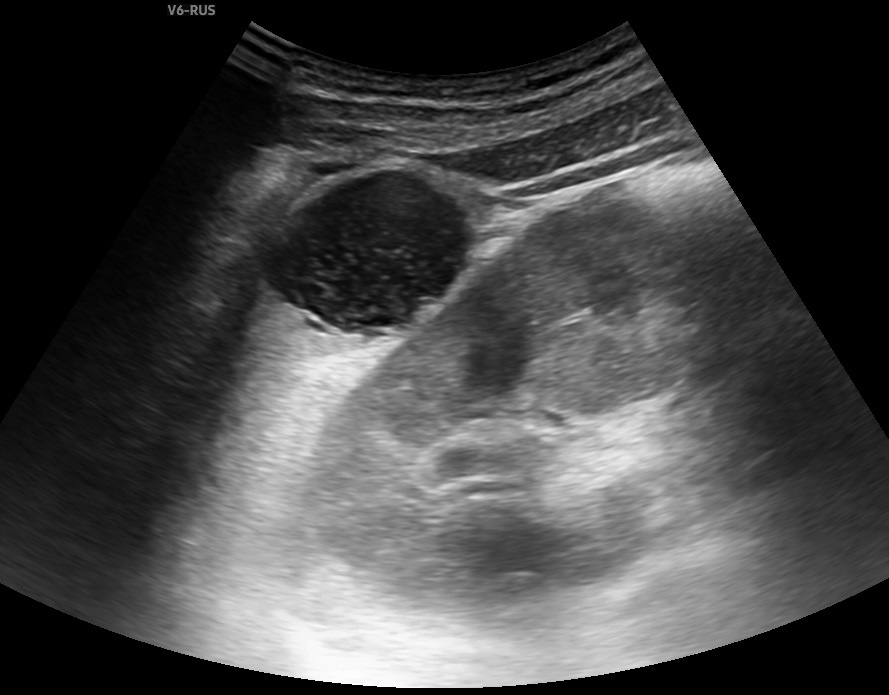

Изображение из свободного доступа Общеизвестно, что чем дольше человек работает, тем больше он знает, тем больше опыта у него есть и, соответственно, тем быстрее он способен принимать решения. Там, где начинающий доктор будет долго "копаться" пытаясь понять ультразвуковую картину, профессионал с опытом примет решение в гораздо более короткий промежуток времени. Но уверенность в своем понимании ультразвуковой картины иногда может сыграть с врачом плохую шутку, когда он, будучи уверен в своих выводах, не уделит достаточно внимания мелочам, которые будут иметь важное значение. Хочу продемонстрировать пример из практики. Пациент более 10 лет наблюдается по поводу объемного образования в селезенке. Предыдущие результаты не представлены, но со слов - опухоль не растет, остаётся всё время в тех же размерах. Все прошедшие годы проводилось только ультразвуковое исследование. При УЗИ селезенки ближе к нижнему полюсу лоцируется образование неправильной округлой формы, значительно сниженной эхоге